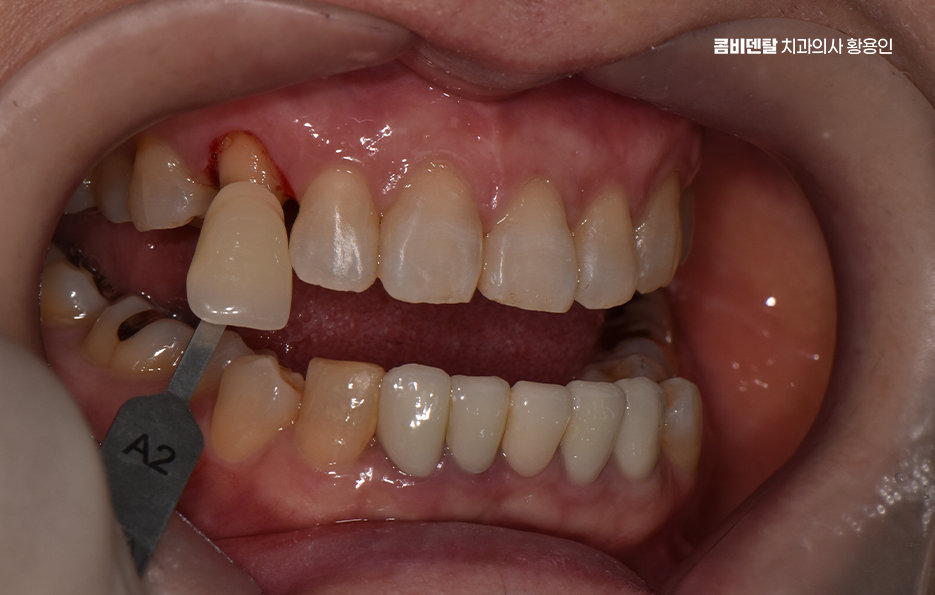

특히 송곳니 크라운 치료가 필요한 상황이라면, 단순히 기능 회복만 생각할 게 아니라 모양과 색감까지 자연스럽게 복원하는 게 중요하겠고 이런 경우에 적합한 방법이 바로 올세라믹이나 지르코니아 크라운을 이용한 심미적인 치료라고 할 수 있어요

크라운 치료는 치아가 많이 손상됐을 때, 또는 신경치료 후 치아가 약해졌을 때 치아를 보호하고 형태를 회복시키기 위한 보철 치료인데 쉽게 말하면 보통 씌우기 치료라고 말하는 치아를 보철물로 전체를 덮는 치료로 송곳니처럼 앞쪽에 위치한 치아는 씌운 게 티 나지 않게 만들어야 하니까 재료 선택이 중요하다는 점에서도 올세라믹과 지르코니아 같은 재료가 주로 활용되고 있었어요

올세라믹 크라운은 말 그대로 금속이 전혀 들어가지 않은 세라믹 재료로 만들어진 크라운으로 금속 없이 순수한 도자기로만 제작되기 때문에 빛 투과성이 자연치아와 거의 비슷하고, 치아 본연의 반투명한 느낌을 재현할 수 있으며 특히 송곳니처럼 햇빛이나 형광등 아래에서 드러나기 쉬운 치아는 빛에 반응하는 느낌이 중요한데 올세라믹은 이런 부분에서 우수한 심미성을 보여주는 재료로 말할 때나 웃을 때 자연스럽게 어우러져서 보철물이 있다는 걸 거의 눈치챌 수 없게 만들어줄 수 있을 정도로 송곳니 크라운 재료에서 심미적인 장점이 있어요

그리고 물론 치료 과정도 중요한데 아무리 좋은 재료를 써도, 본을 잘못 뜨거나 치아 삭제량이 과하면 치아의 수명도 더 줄어들 수 밖에 없고 결과가 자연스럽지 않을 수 있으며 송곳니는 치근이 길고, 뿌리 방향이 독특한 구조를 가지고 있기 때문에 섬세하고 정교한 치료가 중요하기 때문에 경험 많은 치과의사와 함께 하는 것도 중요한 부분이라 할 수 있었어요

송곳니 크라운 치료 시에 자연스러운 결과를 위해 고려해야 할 점으로 또 하나는 잇몸과의 조화로 예를 들어 금속이 들어간 PFM과 같은 보철물은 시간이 지나면서 잇몸 경계에 어둡게 변색되는 현상이 생길 수 있지만 올세라믹은 전혀 금속이 없기 때문에 이런 문제가 없고, 인체 친화적인 소재라 잇몸 자극도 거의 없으며 송곳니는 입술과 접촉이 많은 위치라서 잇몸이 예민한 편인데 올세라믹은 이런 잇몸과도 안정적인 조화를 이루기 때문에 오랜 시간이 지나도 건강한 상태를 유지할 수 있다는 점에서 장점이 있어요